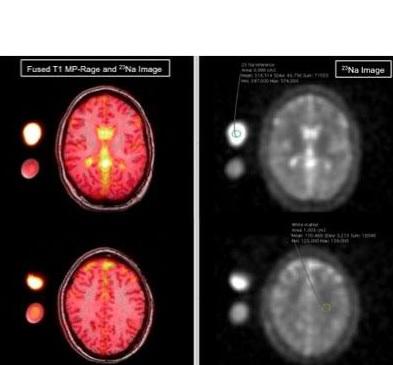

Plus de sel dans le LCR : l’équipe utilise ici une technique d’imagerie par résonance magnétique particulière appelée IRM cérébrale du sodium qui visualise le sodium et confirme que le sodium joue un rôle important dans la chimie du cerveau. L’IRM du sodium montre que chez 12 femmes, âgées en moyenne de 34 ans, diagnostiquées avec migraine et ayant renseigné par questionnaire les caractéristiques de leurs crises (durée, intensité, fréquence, auras…) vs 12 femmes témoins en bonne santé appariées pour l’âge et exemptes de migraines, que :

- les concentrations en sodium des patientes migraineuses sont plus élevées dans le liquide céphalorachidien ;

- en revanche, aucune différence statistique n’est identifiée entre les deux groupes pour les concentrations en sodium dans la matière grise et blanche, le tronc cérébral et le cervelet.